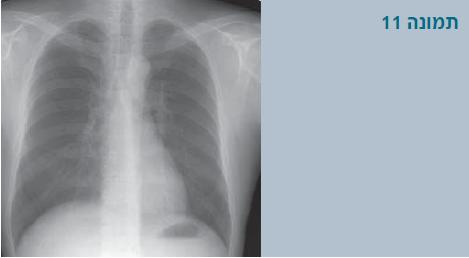

צילום חזה

בצילום חזה חשוב לנסות לראות אם יש קשת אבי-עורקים ימנית. קיום קשת ימנית מכוון אותנו לחשוב על אפשרות של טבעת וסקולרית. עוזר אם משלבים את הצילום גם עם בליעת בריום.

- בתמונה 11: רואים שקע (אינדנטציה) על הקנה משמאל, מתאים לקשת אבי-עורקים שמאלית.

- בתמונה 12: רואים שקע על הקנה מצד ימין שמחשיד מאוד לקשת ימנית.